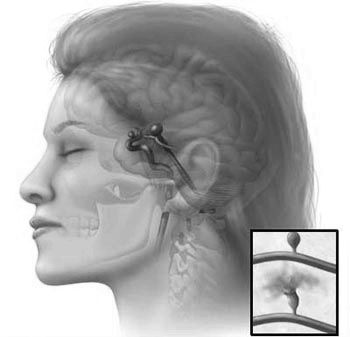

Пацієнтка Тетяна 47 років. Тривало страждала від мігрені (близько п'яти років), завжди лікувалася самостійно, за допомогою народної медицини, трав і різних примочок. Після того, як мігрень не відпускала протягом трьох днів, вирішила звернутися до лікаря. Після повноцінного обстеження, лікар встановив діагноз: Аневризми мозкових судин.

Медики відзначили можливі ризики розвитку інсульту у пацієнтки, було призначено стаціонарне лікування, а також рекомендовано подальше постійне спостереження за станом здоров'я, показниками АТ та ін.

Пацієнт Володимир, 56 років. Звернувся до лікаря після нападу, звичної для нього, мігрені, який супроводжувався нудотою і онімінням одного боку особи. Після детального обстеження, проведення апаратної діагностики встановлено, що чоловік переніс минуще порушення мозкового кровообігу.

Рекомендовано стаціонарне лікування, після якого чоловікові буде необхідна повноцінна реабілітація і постійний контроль над показниками артеріального тиску.